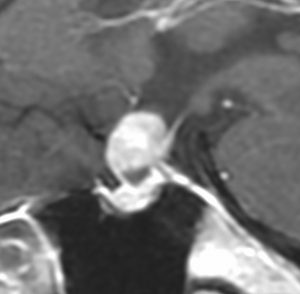

40代の女性に,軽度の両耳側半盲で発生したものです。視交叉と視床下部の下面に腫瘍があり,下垂体柄の位置が全くわからず,下垂体の前葉と後葉は侵されていません。ですから,下垂体柄から発生した腫瘍であり,pituicytomaが強く疑われます。T2ではほぼ等信号,小さなのう胞があり,ガドリニウムで強く増強されます。手術では正常下垂体柄の一部が右側にうすく残っており,幸運にも亜全摘出できて下垂体機能は温存できました。残存腫瘍は増大傾向を示していません。でも,このようなタイプを積極的に摘出すると,汎下垂体機能低下症を招くことが多いので,手術するかどうかの判断はとても難しいです。

下垂体後葉腫瘍の典型的な画像です。下垂体柄(黄色の矢印)が伸びて前方へ偏移しています。またその直下に下垂体前葉(強い白の部分)がみえます。

この例は下垂体柄が認識できて,灰白隆起から発生したとしか思えませんでした

- 画像上は境界が明瞭な腫瘍です

- 腫瘍内部にvascular voidsが多く見えて激しく出血する腫瘍です